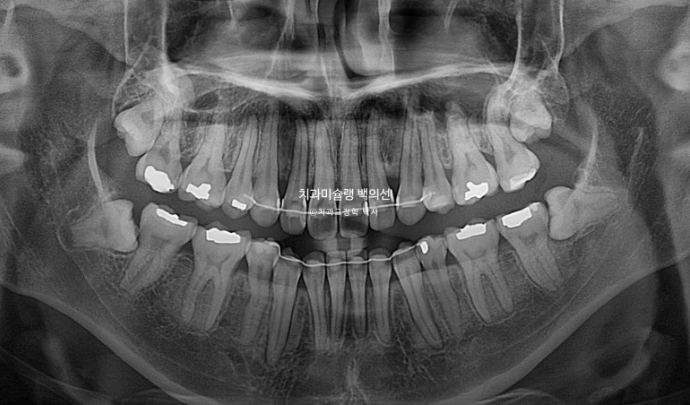

2년 2개월의 치료기간동안 치근흡수는 없었으며 치근평행도는 양호합니다.

초진과 마지막 옆모습 엑스레이 중첩결과를 보며 위 앞니가 약 3mm 합입되며 6mm 후방이동한게 보입니다.

3mm는 거미스마일 교정에서도 꽤 많은 양 함입한 셈인데 치료 중 치근흡수가 없었던 것이 바로 인비절라인 교정의장점입니다.

임상경험으로 비추어 클리피씨 교정에 비해 인비절라인 교정은 치근흡수가 훨씬 적습니다. 물론 연구가 필요한 부분이죠.

앞이 후방이동량이나 함입량보다도 더 주목해야할 점은 하악의 자가회전이 상당이 많이 일어남을 알 수 있습니다.

하관길이는 드라마틱하게 짧아졌고 하악골 회전에 의해 턱끝도 많이 앞으로 나왔습니다.

성장기 아닌 성인에서 양악수술 없이 이정도의 하악 위치 변화는 괄목할만한 결과입니다.